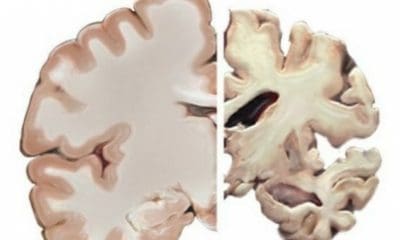

México.-Tras padecer Covid-19, algunos pacientes han reportado secuelas neuropsiquiátricas como delirios, agitación, encefalitis, depresión y ansiedad; según especialistas esto se debe a que el coronavirus entra al Sistema Nervioso Central.